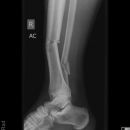

Maisonneuve